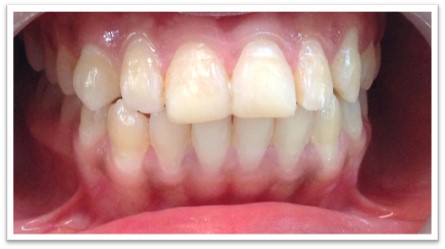

Patient Name:Saba Memon

Tooth Involved :11 , 21

Diagnosis : Ellis Class II Fracture

Treatment : Direct Composite Restoration Using Nanohybrid Composite

Before

After